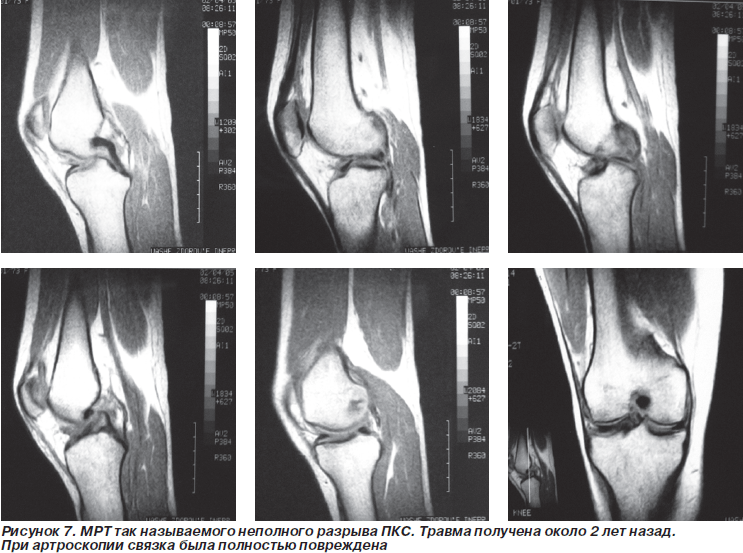

По данным артроскопии разрывы передней крестообразной связки (ПКС) были выявлены у 16 больных. По данным МРТ этих пациентов картина полного разрыва имела место только у 3 из них (18,75 %). У 10 пациентов (62,50 %) по данным МРТ состояние было оценено как неполный разрыв. Еще у 3 больных (18,75 %) повреждений передней крестообразной связки при МРТ-исследовании обнаружено не было.

В то же время при диагностике повреждения крестообразной связки, которая расположена внутрисуставно, МРТ-исследование не обладает столь высокой чувствительностью. Это связано с тем, что не всегда имеет место дислокация связки в полости сустава, вокруг связки наблюдается перифокальный отек синовиальной оболочки. Эти образования дают сигнал высокой интенсивности и затрудняют визуализацию места разрыва. При застарелых повреждениях в ряде случаев имеет место регенерат связки, который не выполняет ее функции. Однако при МРТ он дает сигнал, не всегда отличающийся от нормального, что затрудняет интерпретацию изображения.